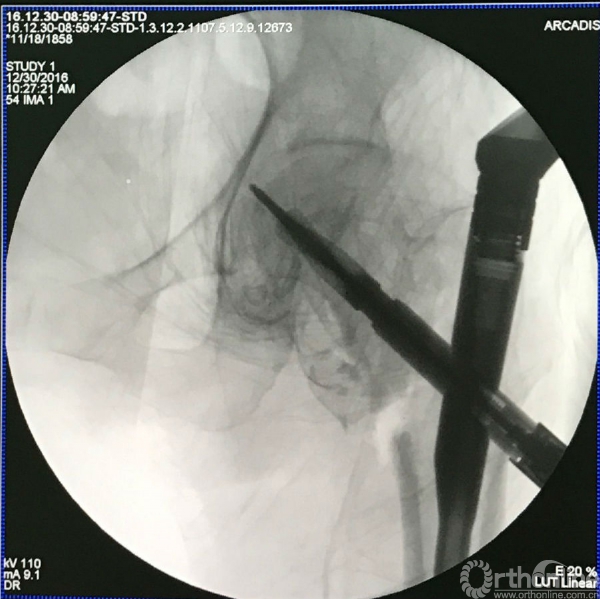

体外复位试一下(外侧是推挤的手的影子),注意:要把牵引架上固定内外旋转的旋钮放松,以便内外旋转对合骨折线复位。

导针的进针点依然遵照标准要求,具体操作要根据手感,针尖触碰到的地方要有敏感感应反馈。

不把远骨折端顶上来,导针很难进入髓腔,或导针插入髓腔后把大转子挡在了远骨折端的前方